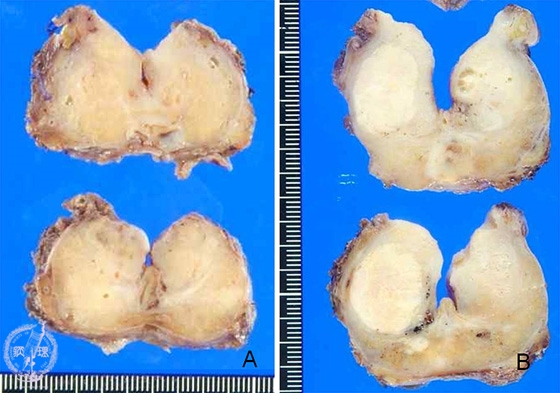

- ★(2)Prostatic cancer (adenocarcinoma, Gleason grading system)

Macroscopic appearance: Prostatic cancer. Solid nodule with blurred margin on cut surface A. Most of the time, the area of prostatic cancer cannot be recognized as clearly as the area of benign prostatic hypertrophy. Therefore usually difficult to distinguish the area of cancer by macroscopic inspection. In some cases, cancer area could be well recognized macroscopically as shown in cut surface B. The blue dotted line highlights the histologically confirmed cancer area in both A and B.